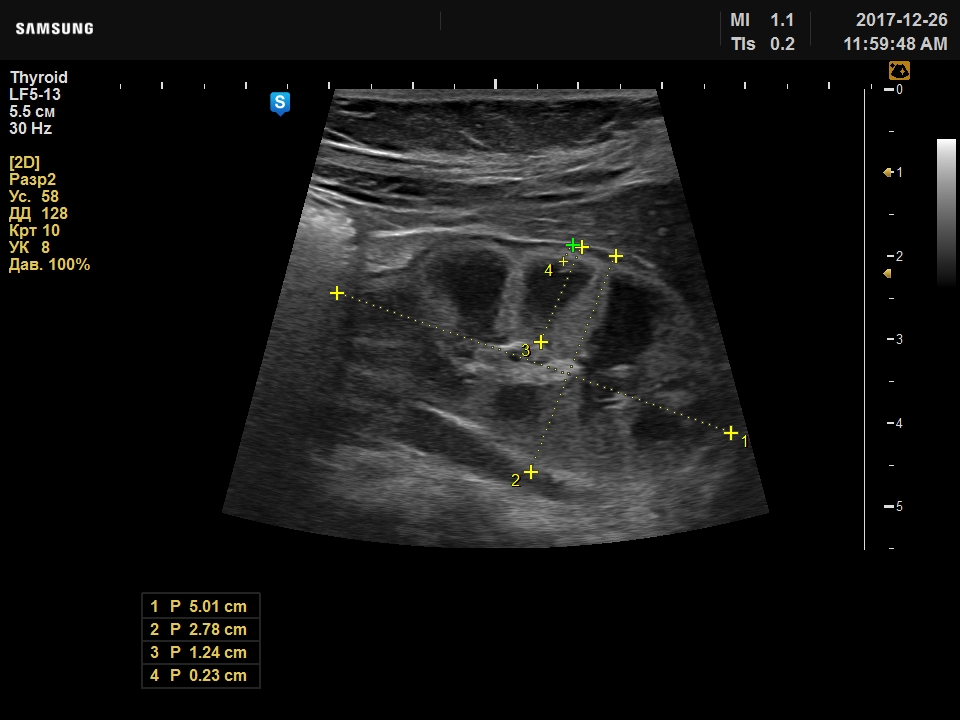

Прошу совета, ребенку 3мес, изменения выявлены около месяца назад в стационаре, где находились по причине желтухи. Вчера были на исследовании у меня: почки нормальных размеров (50х26мм), ЧЛС не расширена, паренхима 11мм, но бросается необычная структура паренхимы, корковый слой повышенной плотности истончен, преобладает мозговой слой в виде больших пирамид, кисты в них не дифференцирую.

Предполагаю дисплазию.

Ваши мысли?

по мне так уз-норма.

Мало вижу почек у детей, но картина у новорожденных отличается от почек детей по-старше. У меня впечатление, что они так и должны выглядеть - фетальная дольчатость, измененное соотношение коркового и мозгового вещества.